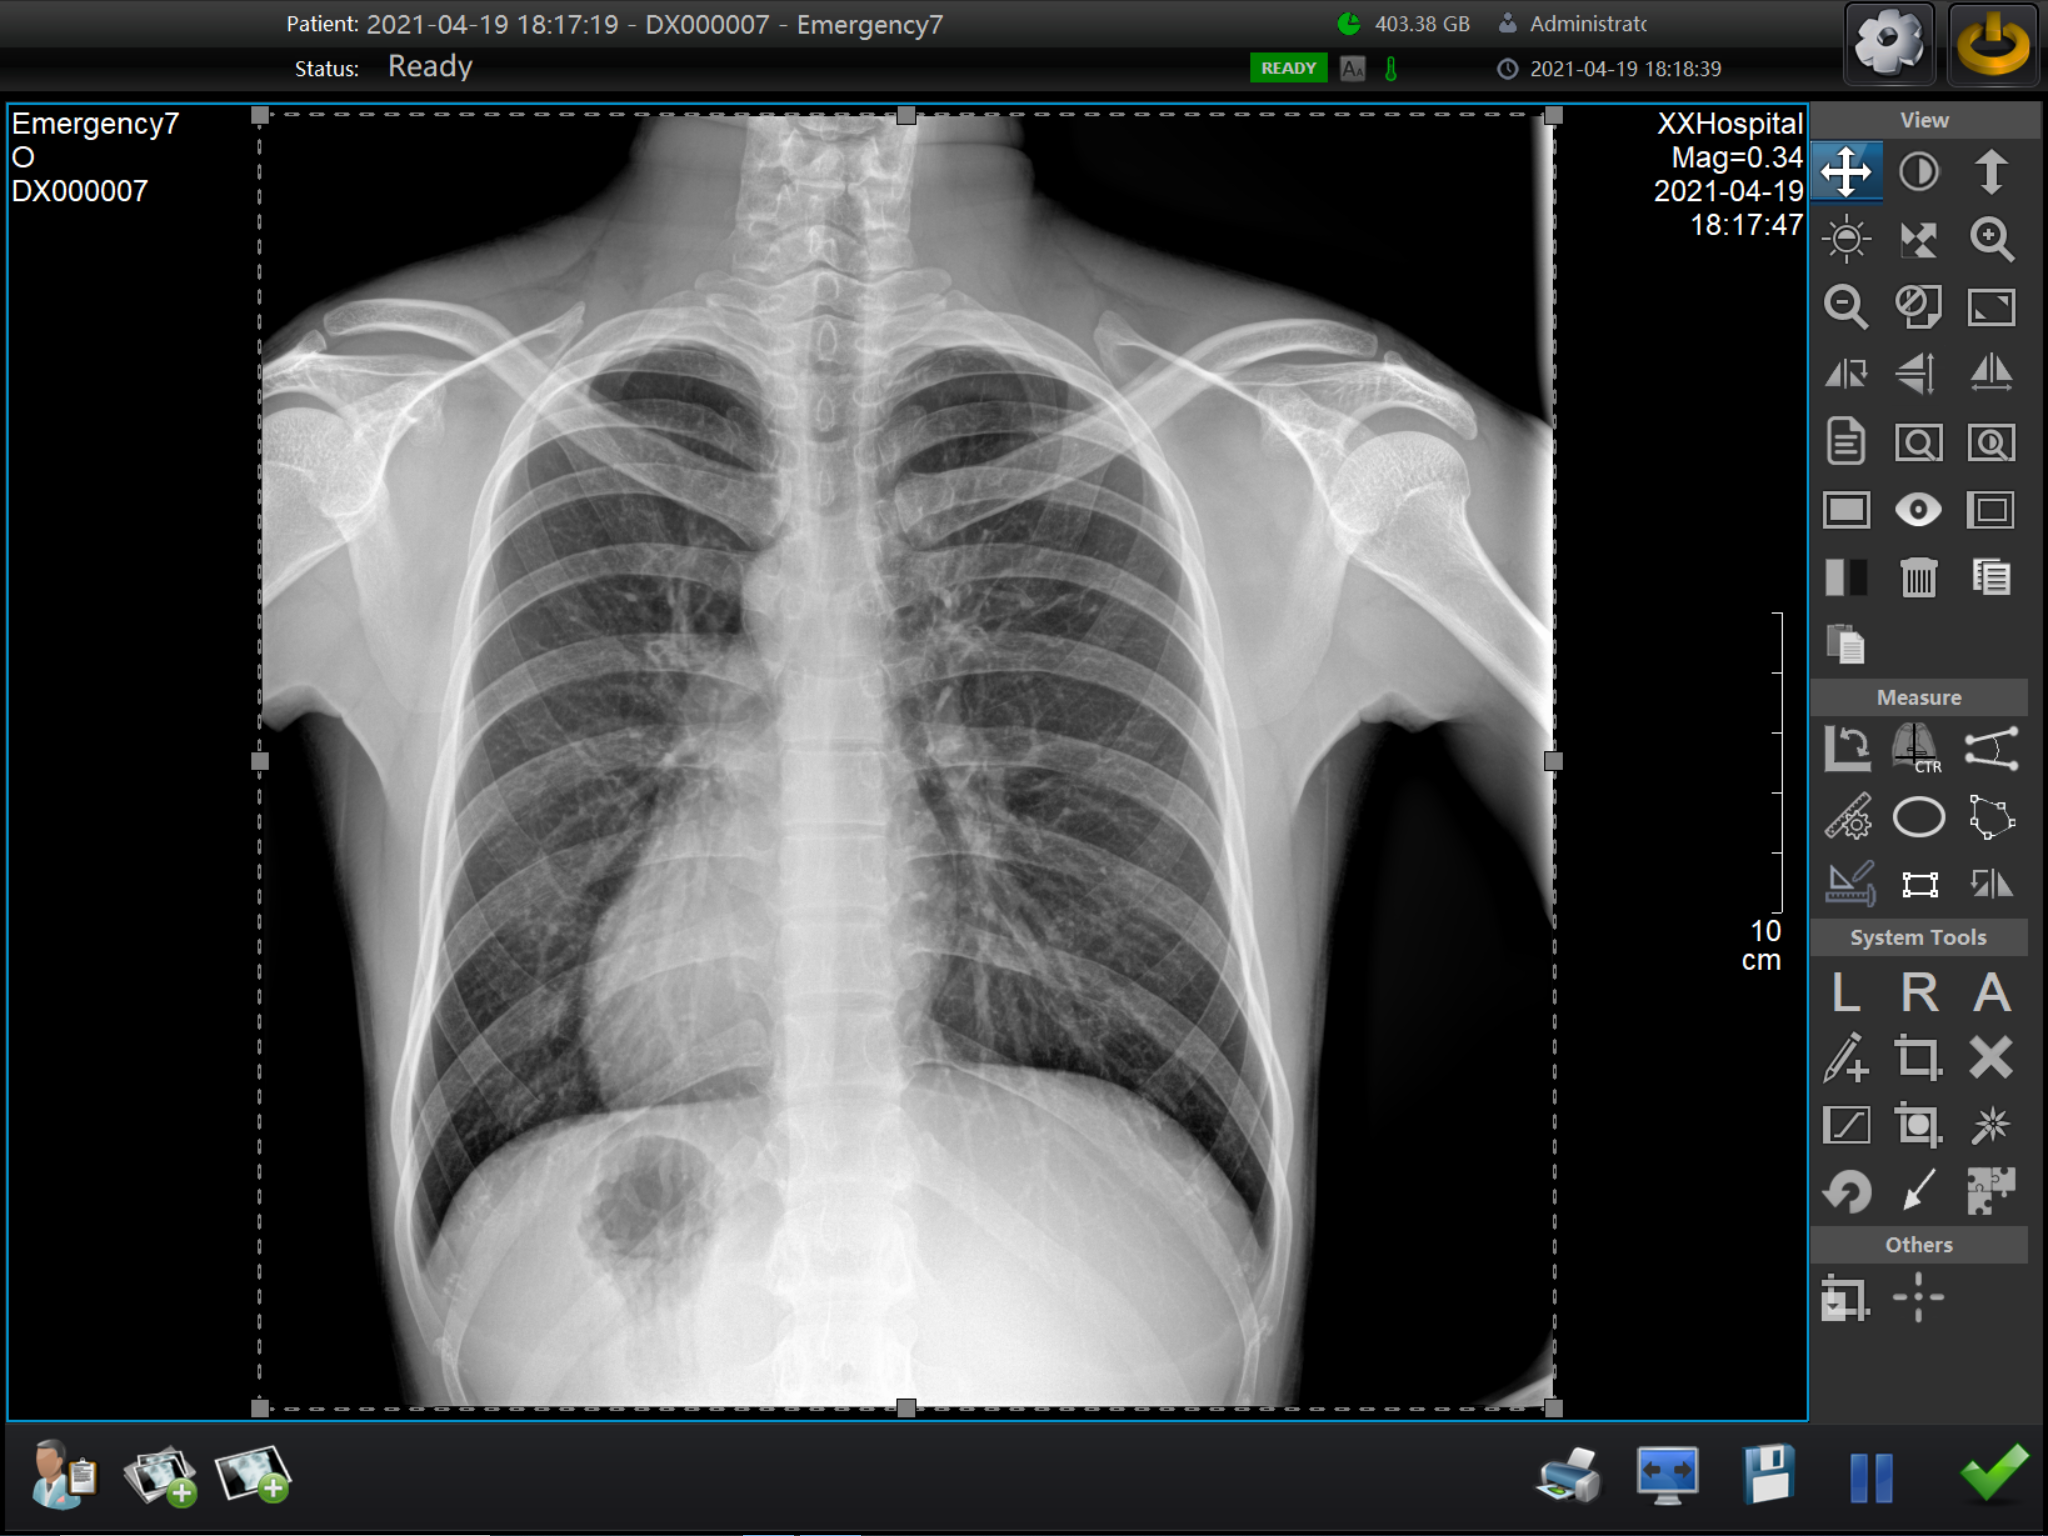

X线摄影中伪影的主要类型。根据产生的原因,伪影可以分为移动伪影、重叠伪影、散射伪影、骨伪影、斑点伪影以及仪器故障导致的伪影等。移动伪影通常发生在物体移动时,由于X线的接收速度较慢,可能导致影像失真。重叠伪影则是在采用正交平面成像时,身体的不同结构可能相互重叠,形成干扰影像。散射伪影则是X射线在穿过身体时发生散射,导致影像中出现与物体实际形态不符的热区或冷区。骨伪影则是由于骨头的高密度特性,使得X射线在穿过骨头时发生散射,产生干扰影像。斑点伪影可能源于数字化平板探测器的损坏或杂质存在。而仪器故障也可能导致影像中出现热区或冷区伪影。